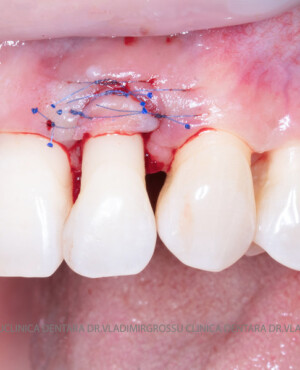

Adiția de gingie (gingivoplastia)

Aditia gingivală este o procedură chirurgicală ce corectează diverse probleme estetice și funcționale, cum ar fi recesiunea gingivală. În implantologia modernă, aditia de țesut moale este utilizată aproape în fiecare intervenție de inserție a implantului dentar pentru a asigura un aspect estetic natural și o bună integrare a implantului în cavitatea bucală.